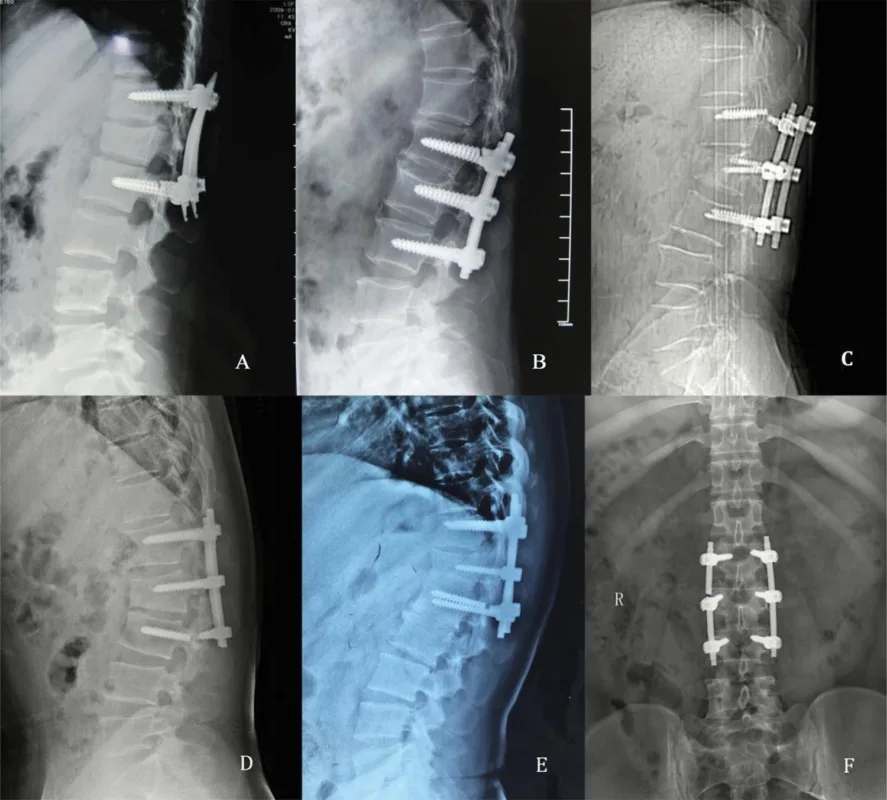

Medical breakthroughs and new materials are often used in orthopedic surgery to help patients do better. Using HA (Hydroxyapatite) covered Break Thru Poly Axial Screws is one example of an improvement. These HA Coated Poly Axial Screws are better than regular screws in several ways, which makes them a valuable addition to spinal implant surgery. […]